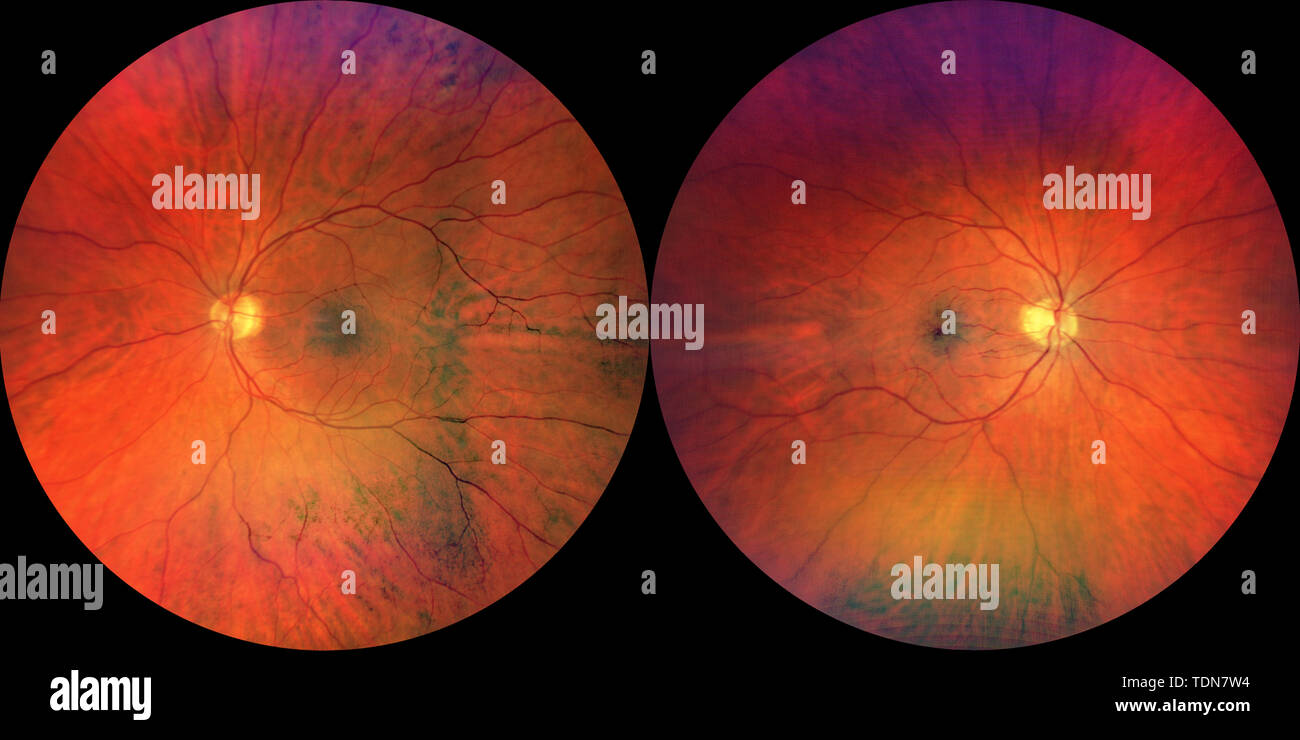

Photograph of the Fundus Oculi: left and right eye Stock Photohttps://www.alamy.com/image-license-details/?v=1https://www.alamy.com/photograph-of-the-fundus-oculi-left-and-right-eye-image249402864.html

Photograph of the Fundus Oculi: left and right eye Stock Photohttps://www.alamy.com/image-license-details/?v=1https://www.alamy.com/photograph-of-the-fundus-oculi-left-and-right-eye-image249402864.htmlRMTDN7W4–Photograph of the Fundus Oculi: left and right eye